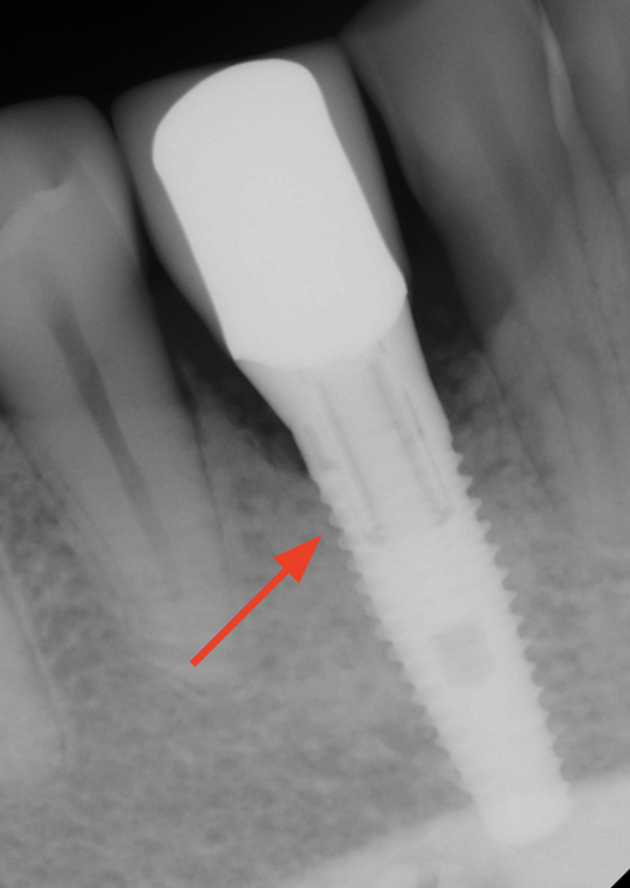

Laser for Periimplantitis

*Follow-up x-rays 9-12 months after treatment